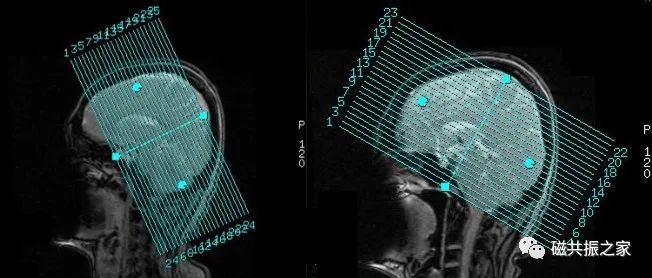

4.头颅的定位方式可根据实际的临床需求采取个性化的扫描定位。

如部分医院横轴位习惯于采用定位线垂直于脑干的方式扫描。

冠状位的定位可以采用平行于脑干,平行于延髓或垂直于颞叶等方式扫描。

7.在实际的临床扫描中如遇到假牙类金属异物无法去除的情况时,可改变成像方位或调整定位线的角度使其尽量避开有干扰的区域。

在实际扫描中改变成像方位或调整定位线的角度使其尽量避开有干扰的区域可有效的改善相应的伪影。